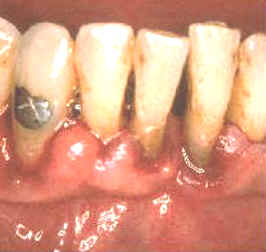

La imagen muestra como quedan las lesiones después

de 14 días del tratamiento. El paciente ha realizado enjuagatorios de

un minuto de duración con

10 ml de chlorhexidine al 0.2% dos veces al día. |

|

Además ha

mejorado su habilidad para cepillar sus dientes. Los dientes están

relativamente libres del

placa dental pero se han manchando

por el clohexidine en las áreas proximales. Los tejidos blandos se

encuentran sanos y aumentaron su firmeza, (resistencia al sondaje) y hay

muy pocas zonas que sangran al sondaje. |

El caso ilustrado demuestra la capacidad del

tejido gingival de sanar cuando se elimina la placa, cemento y dentina infectados y

cálculos. La curación es muy rápida si el paciente coopera con una

buena higiene dental. En este caso particular

el cambio es dramático. |